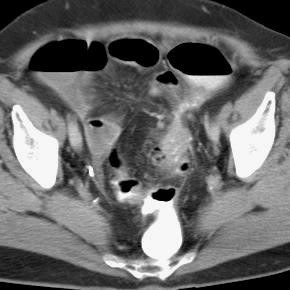

However, it is uncommon for ibs to first develop in women over the age of 50 years. Ovarian cancer is often difficult to detect in its early stages. Can ovarian cancer be found early? Current research suggests this cancer begins in the fallopian tubes and moves to the ovaries, the twin organs that produce a woman's eggs and the main source of the female hormones estrogen and progesterone. While ovarian cancer isn't common, women of any age can get it. There is no way to guarantee that you won't develop cancer in your ovaries, peritoneum (a layer of tissue that lines your abdomen), or fallopian tubes. The optimal abdominal and pelvic ct technique for staging ovarian cancer includes oral contrast media to opacify small bowel and in the absence of contraindications to intravenous contrast media, the use of intravenous contrast media is mandatory. Ovarian cancer may be an outcome of numerous environmental, physiological and psychological read this complete plan for diverticulitis diet… Any of the tissues of the ovary have the. Guide to causes, symptoms, survival rates, ovarian cancer treatment options, fertility problems, prevention guidelines. Ovaries are small organs located on each side of a women's pelvis. Because early stages of ovarian cancer are often not associated with any specific signs or symptoms, many cases are, unfortunately, diagnosed at a later and less treatable stage. Figo ovarian cancer staging effective jan.

Diverticular disease encompasses a set of colonic pathologies that result from abnormal outpouchings of the colonic mucosa (diverticula). It is serous and can be fatal. Ovarian cancer refers to several types of tumour arising from the ovaries. Like many other cancers, when ovarian cancer is found at an early stage (for example, localized to the ovary or fallopian tube) the average survival rate at five years is it is elevated by a large number of disease processes, including but not limited to, diverticulitis, pregnancy, irritable bowel syndrome. It is the leading cause of gynaecological cancer death in the uk. Because early stages of ovarian cancer are often not associated with any specific signs or symptoms, many cases are, unfortunately, diagnosed at a later and less treatable stage. Ovarian cancer is cancer in one or both ovaries. The optimal abdominal and pelvic ct technique for staging ovarian cancer includes oral contrast media to opacify small bowel and in the absence of contraindications to intravenous contrast media, the use of intravenous contrast media is mandatory. Ovaries are the female reproductive organs that produce eggs. In particular, one condition that is often mistaken for ovarian cancer is irritable bowel syndrome (ibs). There is no way to guarantee that you won't develop cancer in your ovaries, peritoneum (a layer of tissue that lines your abdomen), or fallopian tubes. Memorial sloan kettering experts discuss ovarian and breast cancer prevention and treatment in women with a brca mutation. Ovarian cancer is the medical term for abnormal and uncontrollable cell growth within the ovary that proliferates and spreads to other vital organs.